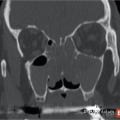

Polypose nasosinusienne

La polypose nasosinusienne est une rhinosinusite diffuse caractérisée par la présence de polypes bilatéraux dans les cavités nasales venant du massif ethmoïdal. Sa physiopathologie repose sur une inflammation chronique de la muqueuse des cavités nasales et sinusiennes marquée par une infiltration éosinophilique plus ou moins…

Rhinosinusites chroniques de l’adulte : nouvelle définition, nouveau diagnostic

La rhinosinusite chronique occupe une place centrale en pathologie rhinologique de l’adulte. Ce terme de « rhinosinusite chronique » a longtemps fait l’unanimité chez les rhinologistes qui se fondaient : sur l’unicité apparente de la muqueuse respiratoire du nez ; sur une communauté d’origine de l’ethmoïde et des…

Tableaux et figures